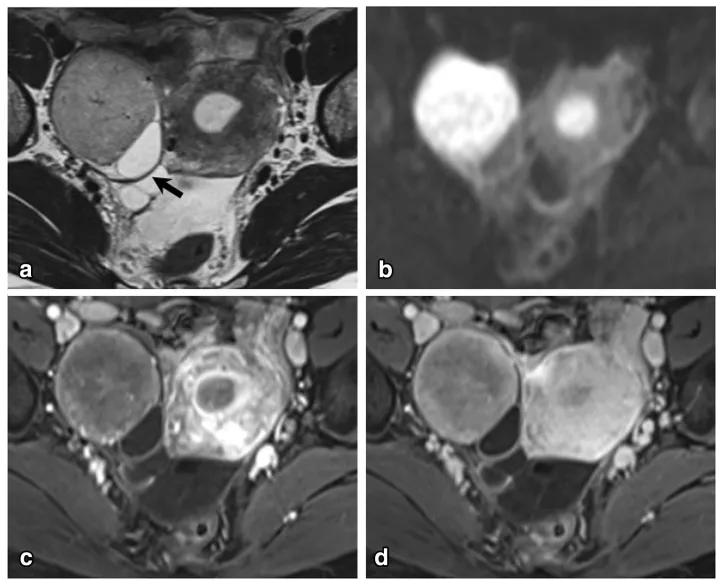

女性,36 岁,睾酮升高,类固醇细胞瘤。T2WI 示右卵巢可见不均匀稍高信号肿物(图 a),增强扫描早期明显强化(图 b)。T1WI 同相位(图 c)及反相位(图 d)可显示肿物内脂质成分,相应 CT 图像呈低密度(图 e)

女,50 岁,卵巢甲状腺肿。左卵巢肿物,T2WI 呈不均匀稍高信号(图 a),增强扫描早期明显强化(图 b),CT 扫描显示囊内成份密度稍高(图 c)。

图 1. 女,22 岁,左侧卵巢硬化性间质瘤。CT 示左侧附件区囊实性巨大肿块,增强后肿瘤周边呈明显持续性强化,肿块周边多发结节及乳头状强化,中央囊性成分未见明显强化。

图 2. 女,42 岁,左侧卵巢硬化性间质瘤。盆腔内巨大囊实性肿块,平扫呈等密度,肿块内部及周边多发絮状及乳头状结节,增强后肿块呈持续性显著强化,向 心性推进,强化绒毛呈「梳齿样」强化。

图 3. 女,19 岁,左侧卵巢硬化性间质瘤。T2WI 轴位(图 3B)示盆腔内囊实性肿块,实性区域与囊变区相交错,呈「梳齿样」表现,肿块边缘见低信号包膜,实性成分呈结节及乳头状等信号,中央囊变区呈裂隙状稍高信号,低信号包膜下见流空血管影(箭头),增强扫描轴位(图 3CD)静脉期及延迟期盆腔内肿块周围实性成分呈显著持续性、向心性强化;中间裂隙状囊变区无强化,表现为「湖岛」征。